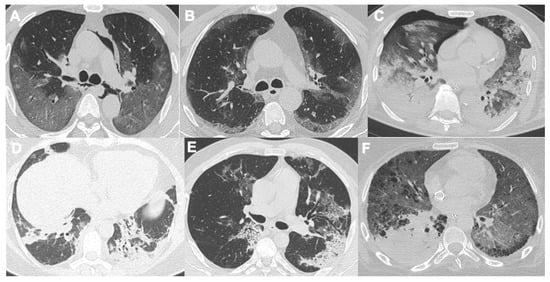

2.2. Acute Respiratory Disease Syndrome

- McGuinness, G.; Zhan, C.; Rosenberg, N.; Azour, L.; Wickstrom, M.; Mason, D.M.; Thomas, K.M.; Moore, W.H. Increased Incidence of Barotrauma in Patients with COVID-19 on Invasive Mechanical Ventilation. Radiology 2020, 297, E252–E262. [Google Scholar] [CrossRef] [PubMed]

- Dalpiaz, G.; Gamberini, L.; Carnevale, A.; Spadaro, S.; Mazzoli, C.A.; Piciucchi, S.; Allegri, D.; Capozzi, C.; Neziri, E.; Bartolucci, M.; et al. Clinical implications of microvascular CT scan signs in COVID-19 patients requiring invasive mechanical ventilation. Radiol. Med. 2022, 127, 162–173. [Google Scholar] [CrossRef] [PubMed]